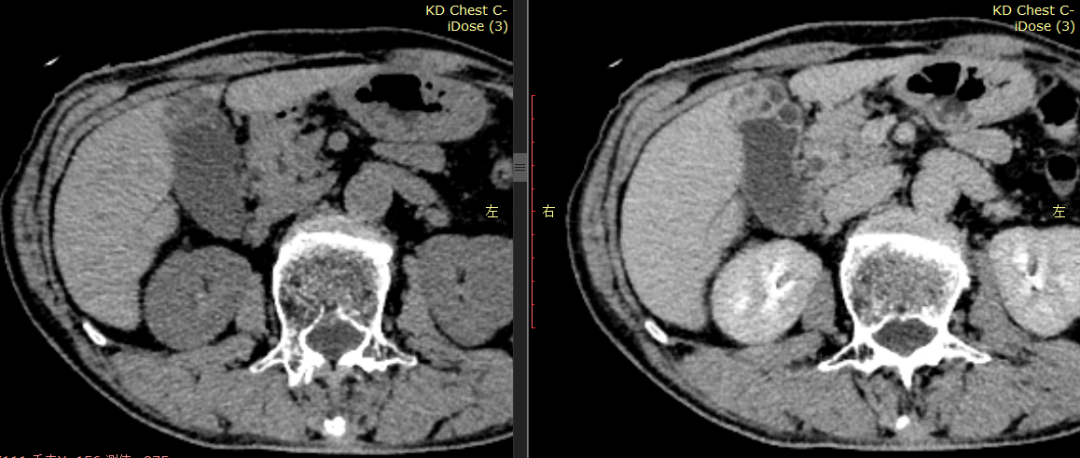

CASE 3